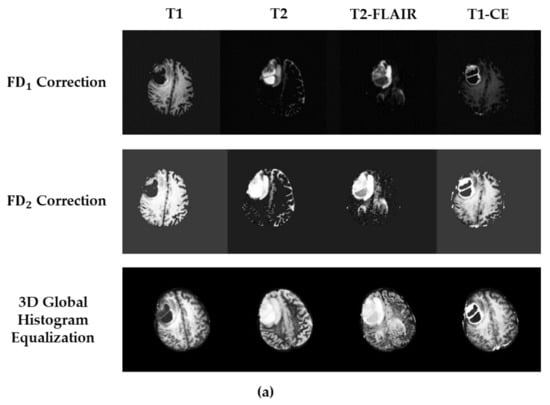

| Preprocessing Method | Dice Score | Computational Time (min) | ||

|---|---|---|---|---|

| Training Stage | Validation Stage | |||

| 3D Global Histogram Equalization | WT: | 0.9220 | 0.8002 | 138 |

| TC: | 0.9419 | 0.7688 | ||

| ET: | 0.9142 | 0.6365 | ||

| correction | WT: | 0.9491 | 0.8337 | 140 |

| TC: | 0.9757 | 0.7976 | ||

| ET: | 0.9559 | 0.6802 | ||

| correction | WT: | 0.9336 | 0.8433 | 141 |

| TC: | 0.9773 | 0.8041 | ||

| ET: | 0.9606 | 0.6848 | ||